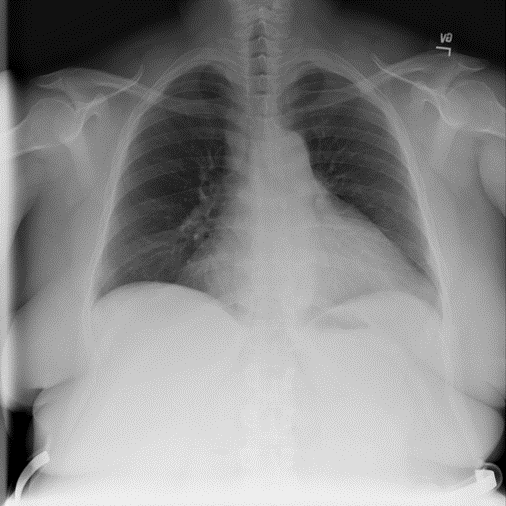

Figure 9: Typical CXRs with pneumonia-like lung opacity from among the top 1,000 CXRs most likely to have an abnormality according to the logarithm posterior probability out of the 13,863 abnormal CXRs. The lesion is indicated with a red arrow if applicable.

Figure 9 shows CXRs suggested to have pneumonia-like lung opacity with the logarithm posterior probability. These CXRs are the top 1,000 CXRs most likely to have an abnormality out of the 13,863 abnormal CXRs.